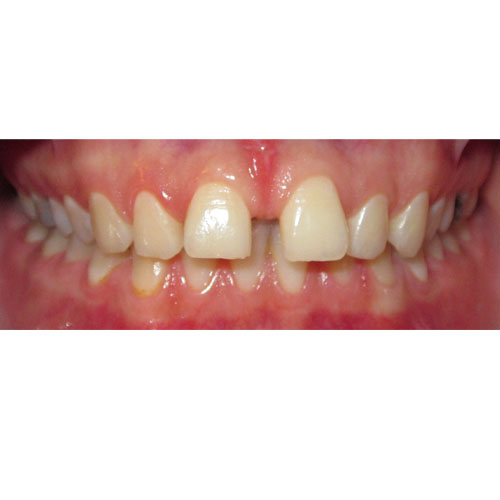

Nasze rezultaty